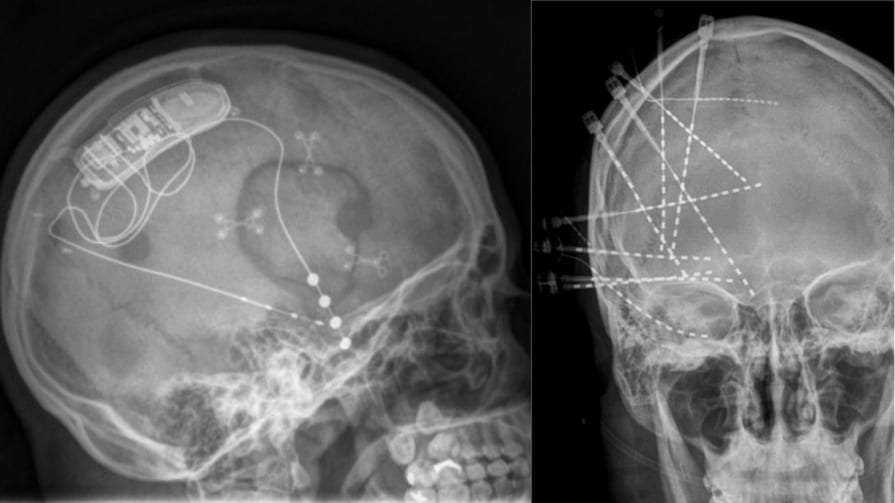

1月18日に『Nature Medicine』に掲載された論文によれば、脳内に埋め込んだ電極で「喜びの回路」を刺激することで、難治性のうつ病が数分で改善したとのこと。